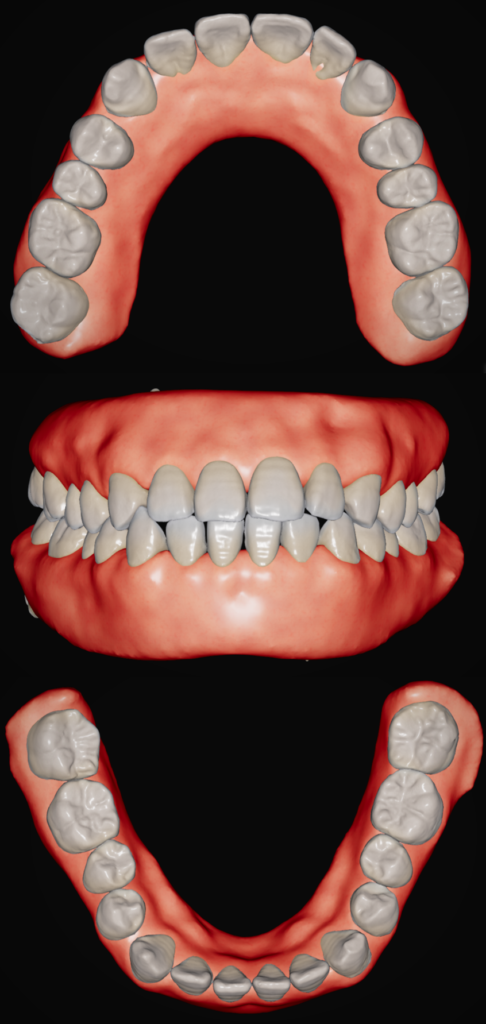

③口腔内スキャン

デジタル上で歯型を取ります。スキャンデータをCTと合わせることで、口腔内の状態を正確に再現できます。

抜歯したスペースや歯列拡大などを行った場合、どういう結果になるかなど主に治療計画を立てる際に必要になります。